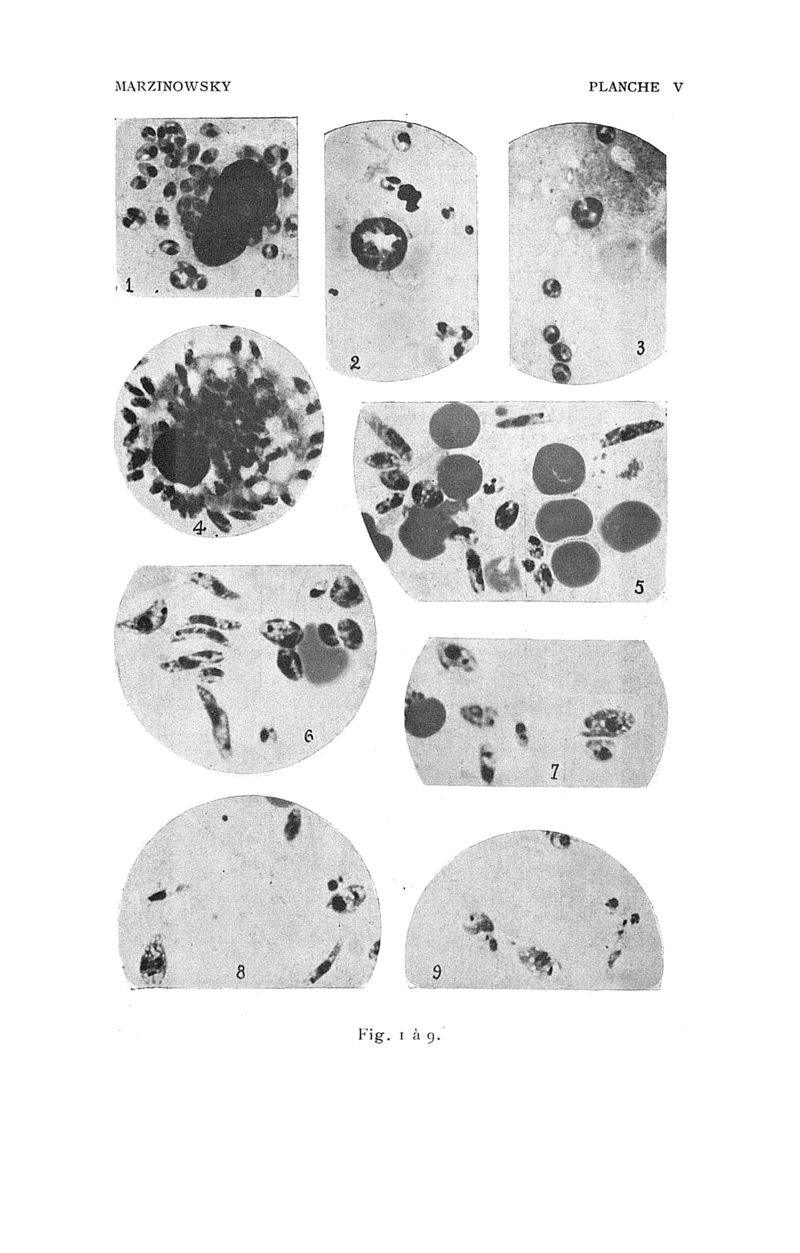

Bulletin de la Société de pathologie exotique

1909, tome 02. - Paris : Masson, 1909.